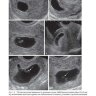

Примеры страниц из книги "Ультразвуковая дифференциальная диагностика в акушерстве и гинекологии" - Биссет Р.

Книга содержит информацию об анатомических особенностях строения, ультразвуковой визуализации матки, придатков, методиках сканирования, новейших технологиях при неизмененных состояниях, функциональных отклонениях, патологиях, выявляемых при мультипараметрическом УЗИ. Главы включают в себя обсуждение проблемных вопросов, практические советы и рекомендации, а также наиболее актуальные литературные источники.

Издание хорошо иллюстрировано. Большое количество схем, таблиц, рисунков, эхограмм позволяет более четко понимать визуальную картину многочисленных изменений, наиболее часто выявляемых при эхографии органов малого таза в клинической практике в норме и при патологии.